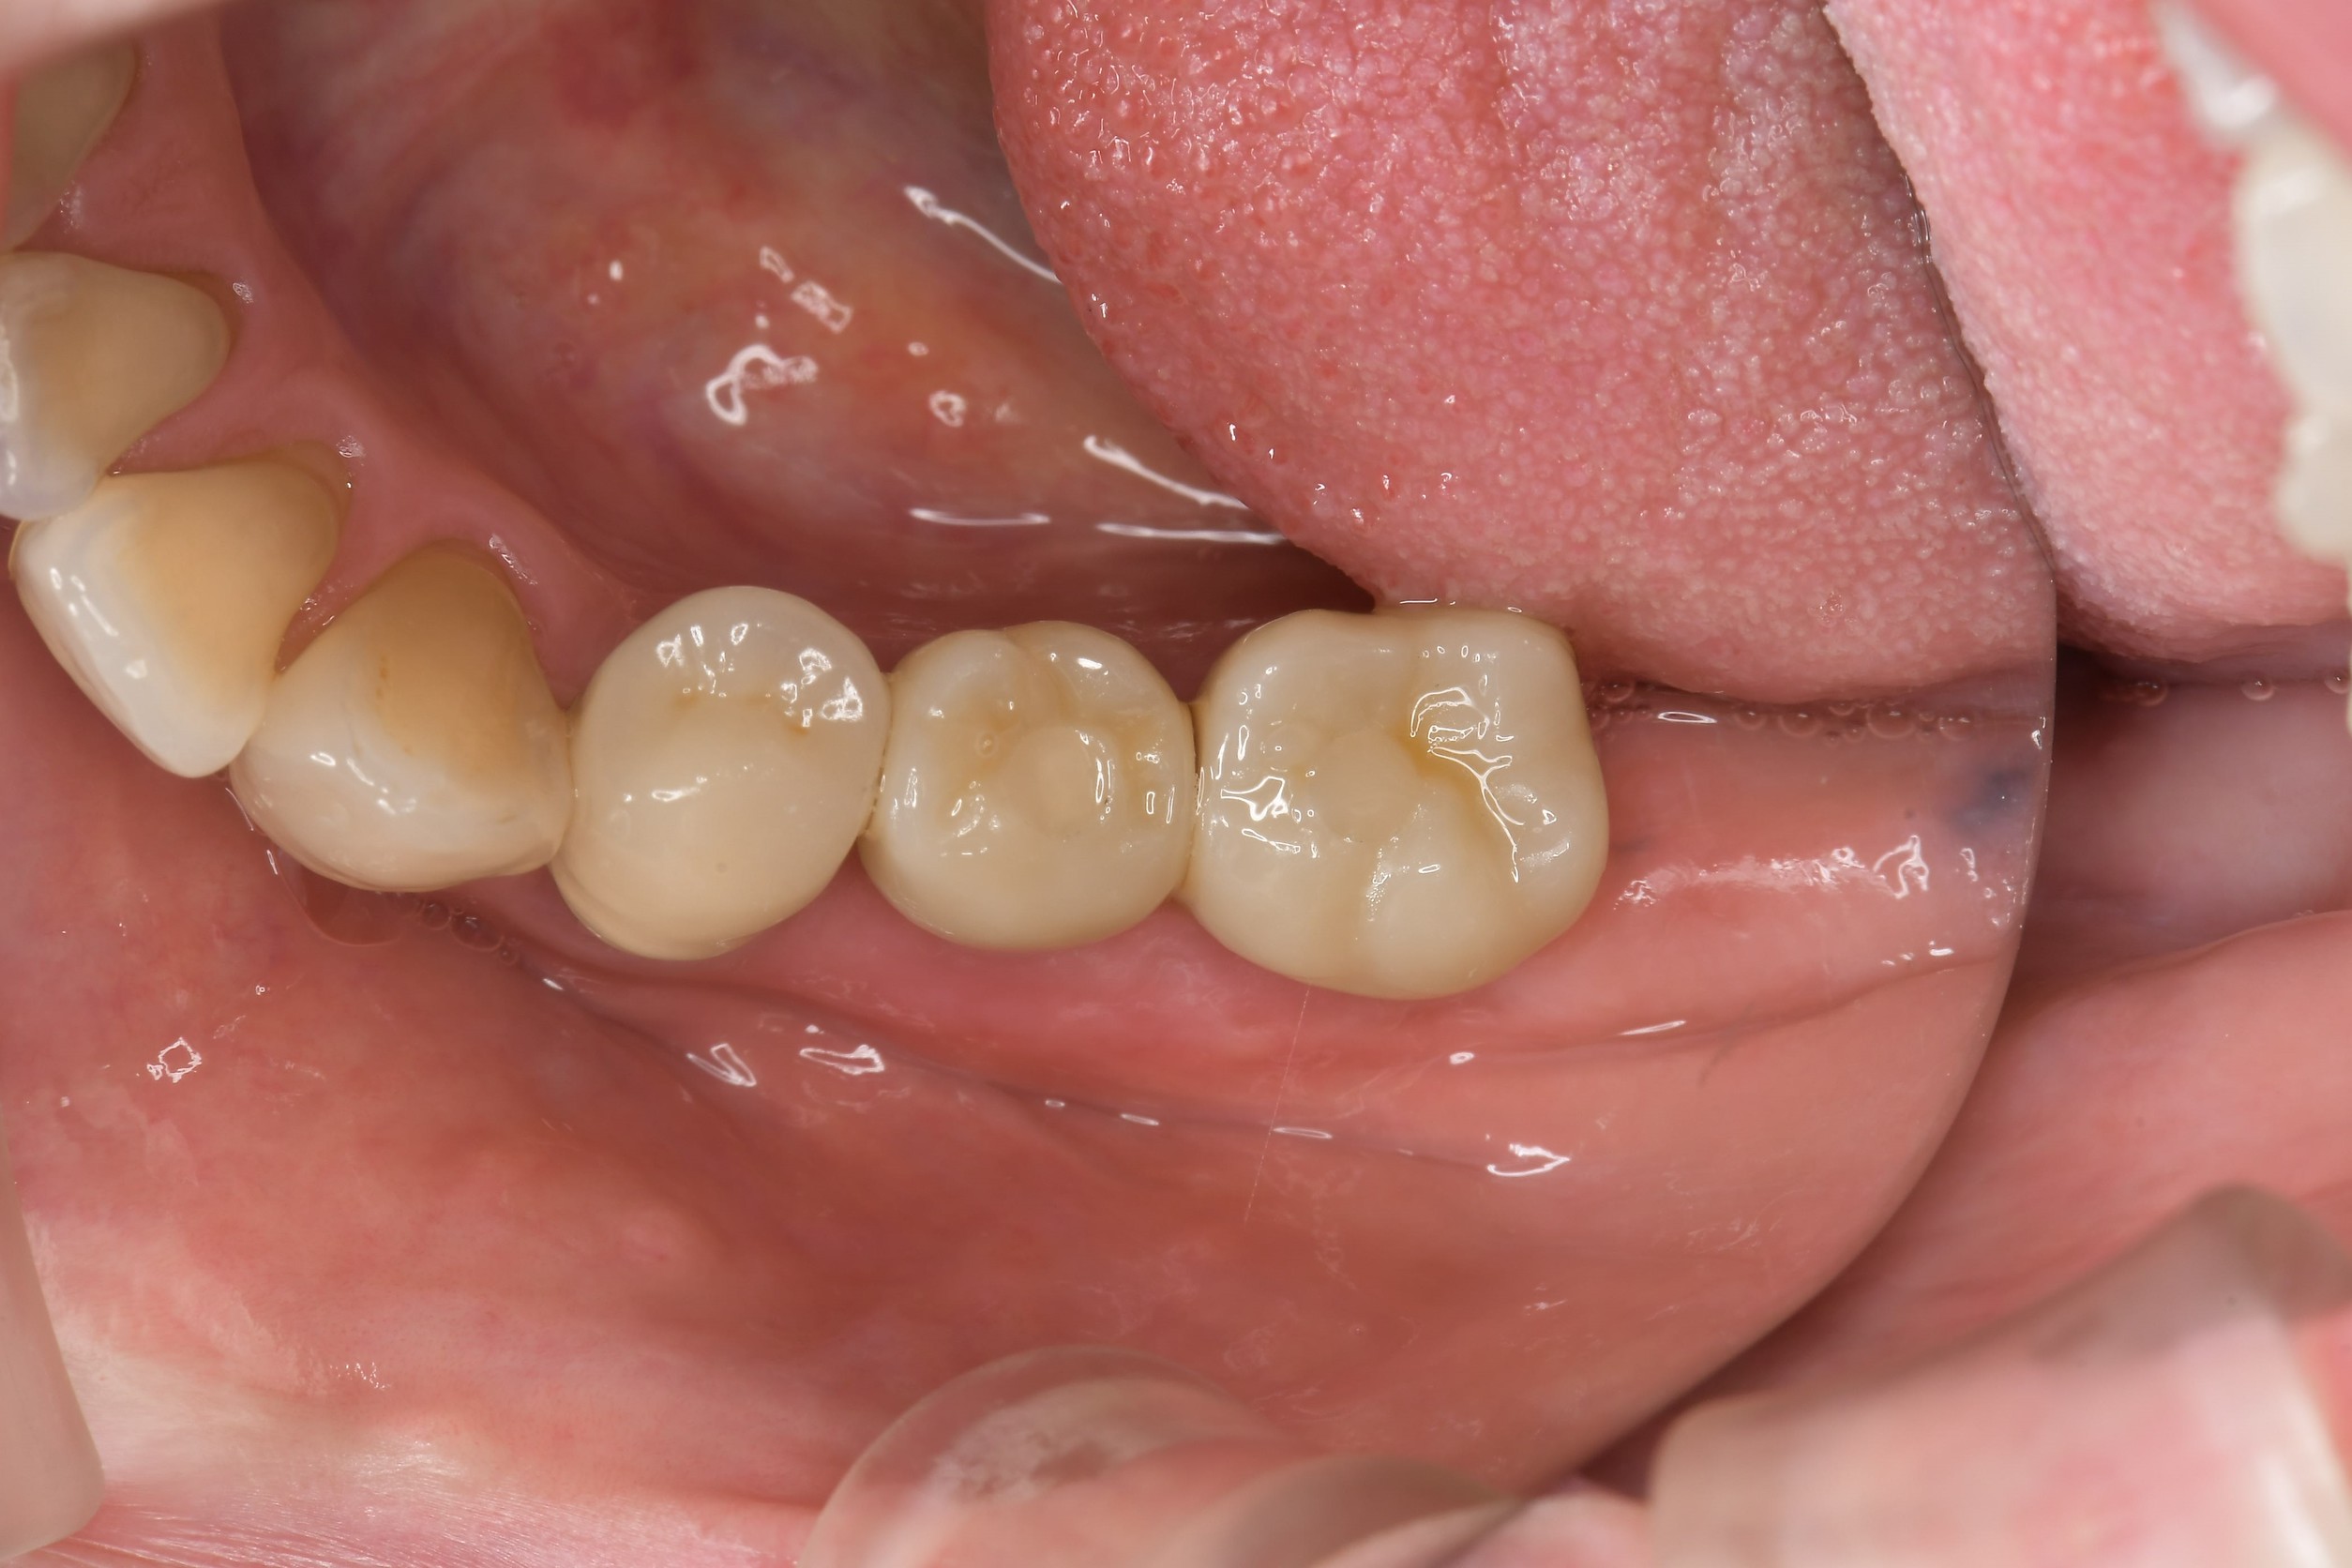

手術から10日後の検診では、抜歯した部分の歯ぐきはすでに良好な状態まで回復していました。

術後の経過写真からも、切開を行わない処置であったため、出血や腫れ、術後の痛みが比較的少ない状態で経過していることが確認できます。外科処置を一度で終えられた点は、お仕事や家事で忙しい患者さんにとって負担軽減につながりました。

今後は、インプラントが骨と結合するのを待ち、最終的な被せ物を装着していきます。左下の噛み合わせがしっかり戻ることで、他の残っている健康な歯を守ることにも繋がります。